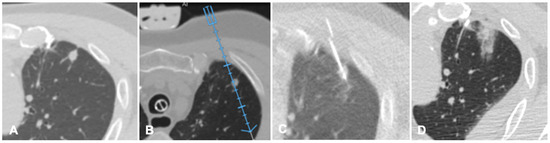

Figure 2. Case of a patient with liver metastases from renal cancer treated with microwave ablation (MWA). (A) Axial view during portal phase of the preoperative contrast enhanced Computed Tomography (CECT) showing a 6 mm enhancing lesion of segment I (white arrow); (B) Live multiplanar reconstruction of the same source CT (left side) using fusion imaging (FI) with intraoperative ultrasound (right side). In both views target lesion is marked by a green spot while the MWA needle is marked by two solid arrows in the ultrasound image (right). (C) FI during MWA of the lesion in the liver segment I. Arrow points out the area of gas formation at the tip of the ablation needle. (D) An axial view of the CECT control the day after the procedure. Arrow points out the area of ablation of the liver segment I.

MRI and CT are both used as reference data set for FI; FI imaging with conventional US and liver CT/MR images improves the detection rate of HCC of 45% and, therefore, the procedure’s feasibility after FI [14,20]. However, some studies have shown the superiority of MRI with hepatobiliary phase to CT images for the identifications and definitions of hepatic lesions, especially in small lesions less than 1 cm [21]. Nevertheless, very promising preliminary data are available regarding US/Cone beam CT (CBCT) FI [22]. It is technically feasible and appears to be an effective image guidance modality for achieving correct targeting and ablation of small lesions not clearly visible at US (Figure 2).